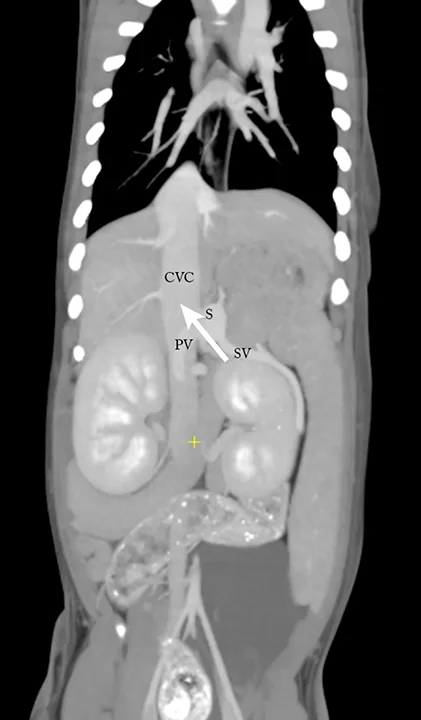

After 2 weeks, CT angiography is performed, and a splenocaval shunt (Figure 1) and multiple cystoliths are revealed. Exploratory laparotomy is performed, the splenocaval shunt is identified, and an ameroid ring constrictor is placed to achieve gradual occlusion (Figure 2). A liver biopsy is obtained, and a routine cystotomy is performed to remove the cystoliths. All samples are submitted for analysis.

FIGURE 1

Sagittal CT image depicting the relationship among the portal vein (PV), splenic vein (SV), caudal vena cava (CVC), and splenocaval portosystemic shunt (S). Portal blood flows through the shunt into the CVC (arrow).